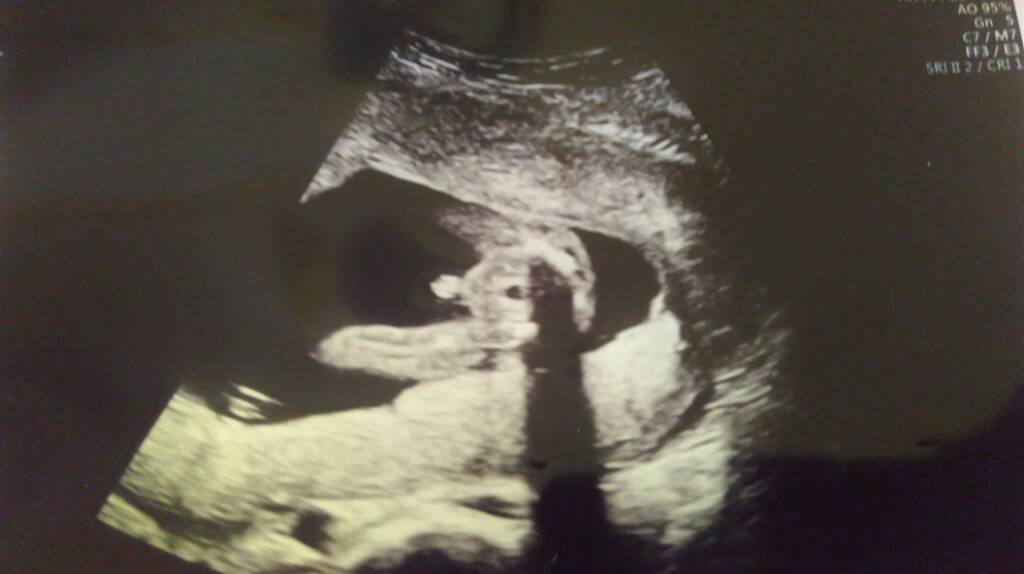

Fajny siurek